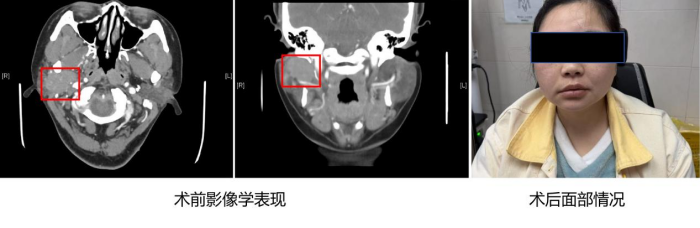

周定刚副主任医师详细了解患者病史后,为郭芙安排了腮腺增强CT检查。结果显示:“其右侧腮腺存在一个鸡蛋大小、跨叶生长的不规则团块,边界模糊,增强后肿块呈渐进性强化,边缘可见多发血管影”,周定刚高度怀疑为腮腺恶性肿瘤。更棘手的是,肿瘤位于腮腺浅叶与深叶之间,紧邻面神经,手术中稍有不慎就可能损伤面神经,导致口角歪斜、闭眼困难等后遗症。

周定刚耐心向患者及家属讲解手术风险与方案,为郭芙实施全麻下“腮腺及肿瘤切除+面神经松解+Ⅱ区淋巴结清扫术”。术中可见肿块位于面神经深面,并压迫面神经主干。周定刚仔细分离面神经分支,将肿瘤组织切除,解除面神经压迫。术后病理检查证实为腮腺黏液表皮样癌。由于手术精准,患者术后恢复良好,面神经功能保留良好。